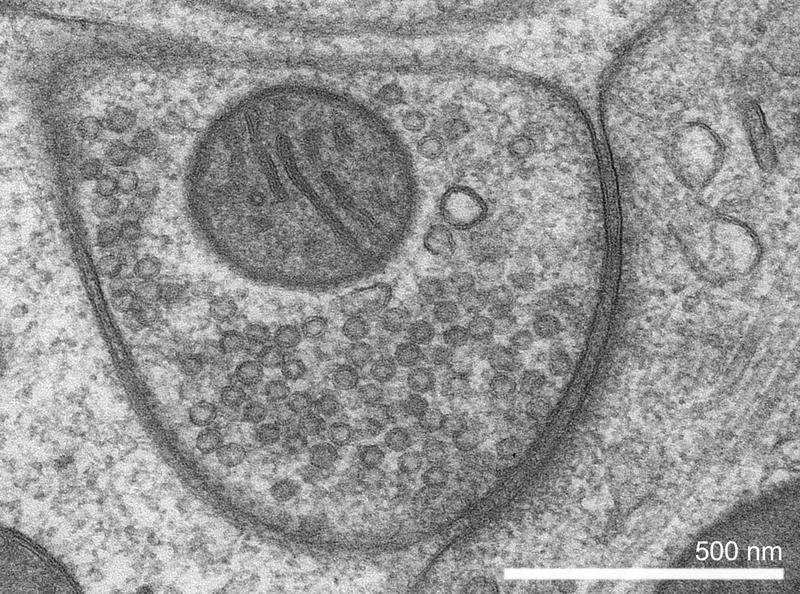

Das VGAT-Gen enthält den Bauplan für einen molekularen Transporter im Gehirn, der den wichtigen Botenstoff GABA in die Botenstoffbehälter innerhalb einer Nervenzelle – die sogenannten synaptischen Vesikel – transportiert. Dort wird GABA aufbewahrt und ausgeschüttet, wenn ein Signal an eine benachbarte Zelle weitergeleitet werden soll.

„Wir konnten nachweisen, dass die Veränderungen im VGAT-Gen vor allem dazu führen, dass der Transporter deutlich geringere Mengen an GABA in die Vesikel befördert. Entsprechend weniger davon steht dann bereit, um Signale weiterzuleiten. Das stört das Gleichgewicht der Botenstoffe und damit auch das Gleichgewicht zwischen den sogenannten hemmenden und erregenden Nervenzellen. Dies kann zur Überaktivität von Nervenzellen führen“, erklärt die Projektgruppenleiterin.